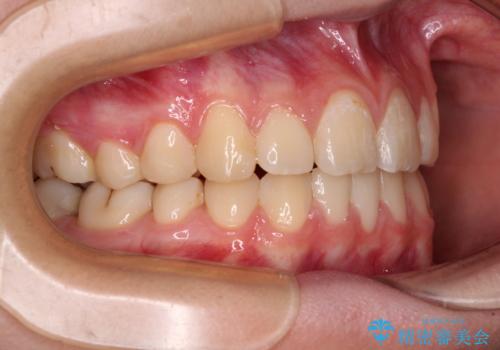

まずは補助装置を用いて八重歯を改善し、インビザラインにて歯列を整えましたが、当初の懸念が的中し、臼歯部の咬合を安定させることができませんでした。

海外留学の予定もあったため、後半は上下ワイヤー装置にて矯正治療を継続し、違和感なく咬合させることとなりました。